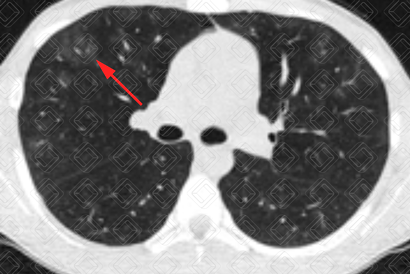

Texto alternativo para a imagem Créditos: Dra. Elazir Mota - Rio de Janeiro/RJ

Descrição das imagens: Tomografia computadorizada do tórax evidenciando tênues lesões em vidro fosco (setas vermelhas) dispersas pelo parênquima pulmonar, por hemorragia alveolar. Caso confirmado de leptospirose com apresentação pulmonar.

• Tomografia computadorizada de tórax: Opacidades em vidro fosco, pavimentação em mosaico (padrão caracterizado por áreas em vidro fosco associado a espessamento dos septos interlobulares) e consolidações são os achados mais frequentemente observados e traduzem a presença de hemorragia alveolar (uma complicação que ocorre na leptospirose), como demonstrado nas imagens acima. Sua distribuição é preferencialmente periférica, subpleural e nas regiões póstero-inferiores dos pulmões. Cabe lembrar, no entanto, que são achados de imagem inespecíficos, assim como na radiografia. O diagnóstico só pode ser sugerido diante de uma boa história clínica.